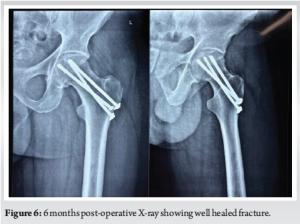

Follow-up X-rays were taken at 3 months, 6 months, and 1 year. On the last follow-up at the end of 1 year, the patient has regained full ROM of the hip. Patient is able to squat, sit cross-legged, and is able to walk unaided (Fig. 6 and 7).